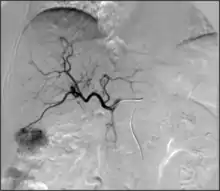

• Angiography: Imaging the blood vessels to look for abnormalities with the use of various contrast media, including iodinated contrast, gadolinium based agents, and CO2 gas.[3]